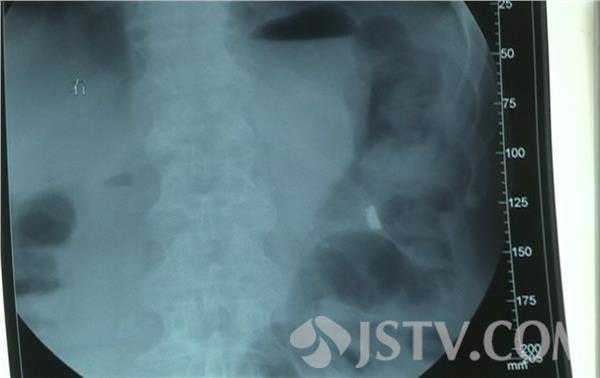

日前,江苏淮安一位年过七旬的张老太吃完儿媳做的面条,喝了一口面汤,在仰头的一瞬间,假牙竟然跟着面汤被喝了下去。紧急送医后,医院发现,假牙已经和牙托钢丝一起进入了老人的食道。经过一个多小时操作,医生借助食道内镜取出了这一副要命的假牙。医生介绍,吃饭时吞咽进假牙的情况时有发生,有些甚至要转至胸外科'开胸取牙', 真的是相当危险。因此,佩戴假牙的人士要时刻关注自己的假牙是否松动,如有松动一定要及时去医院进行紧固。万一吞进了假牙,千万不要强行吞咽,应该紧急到医院拍片就诊 。